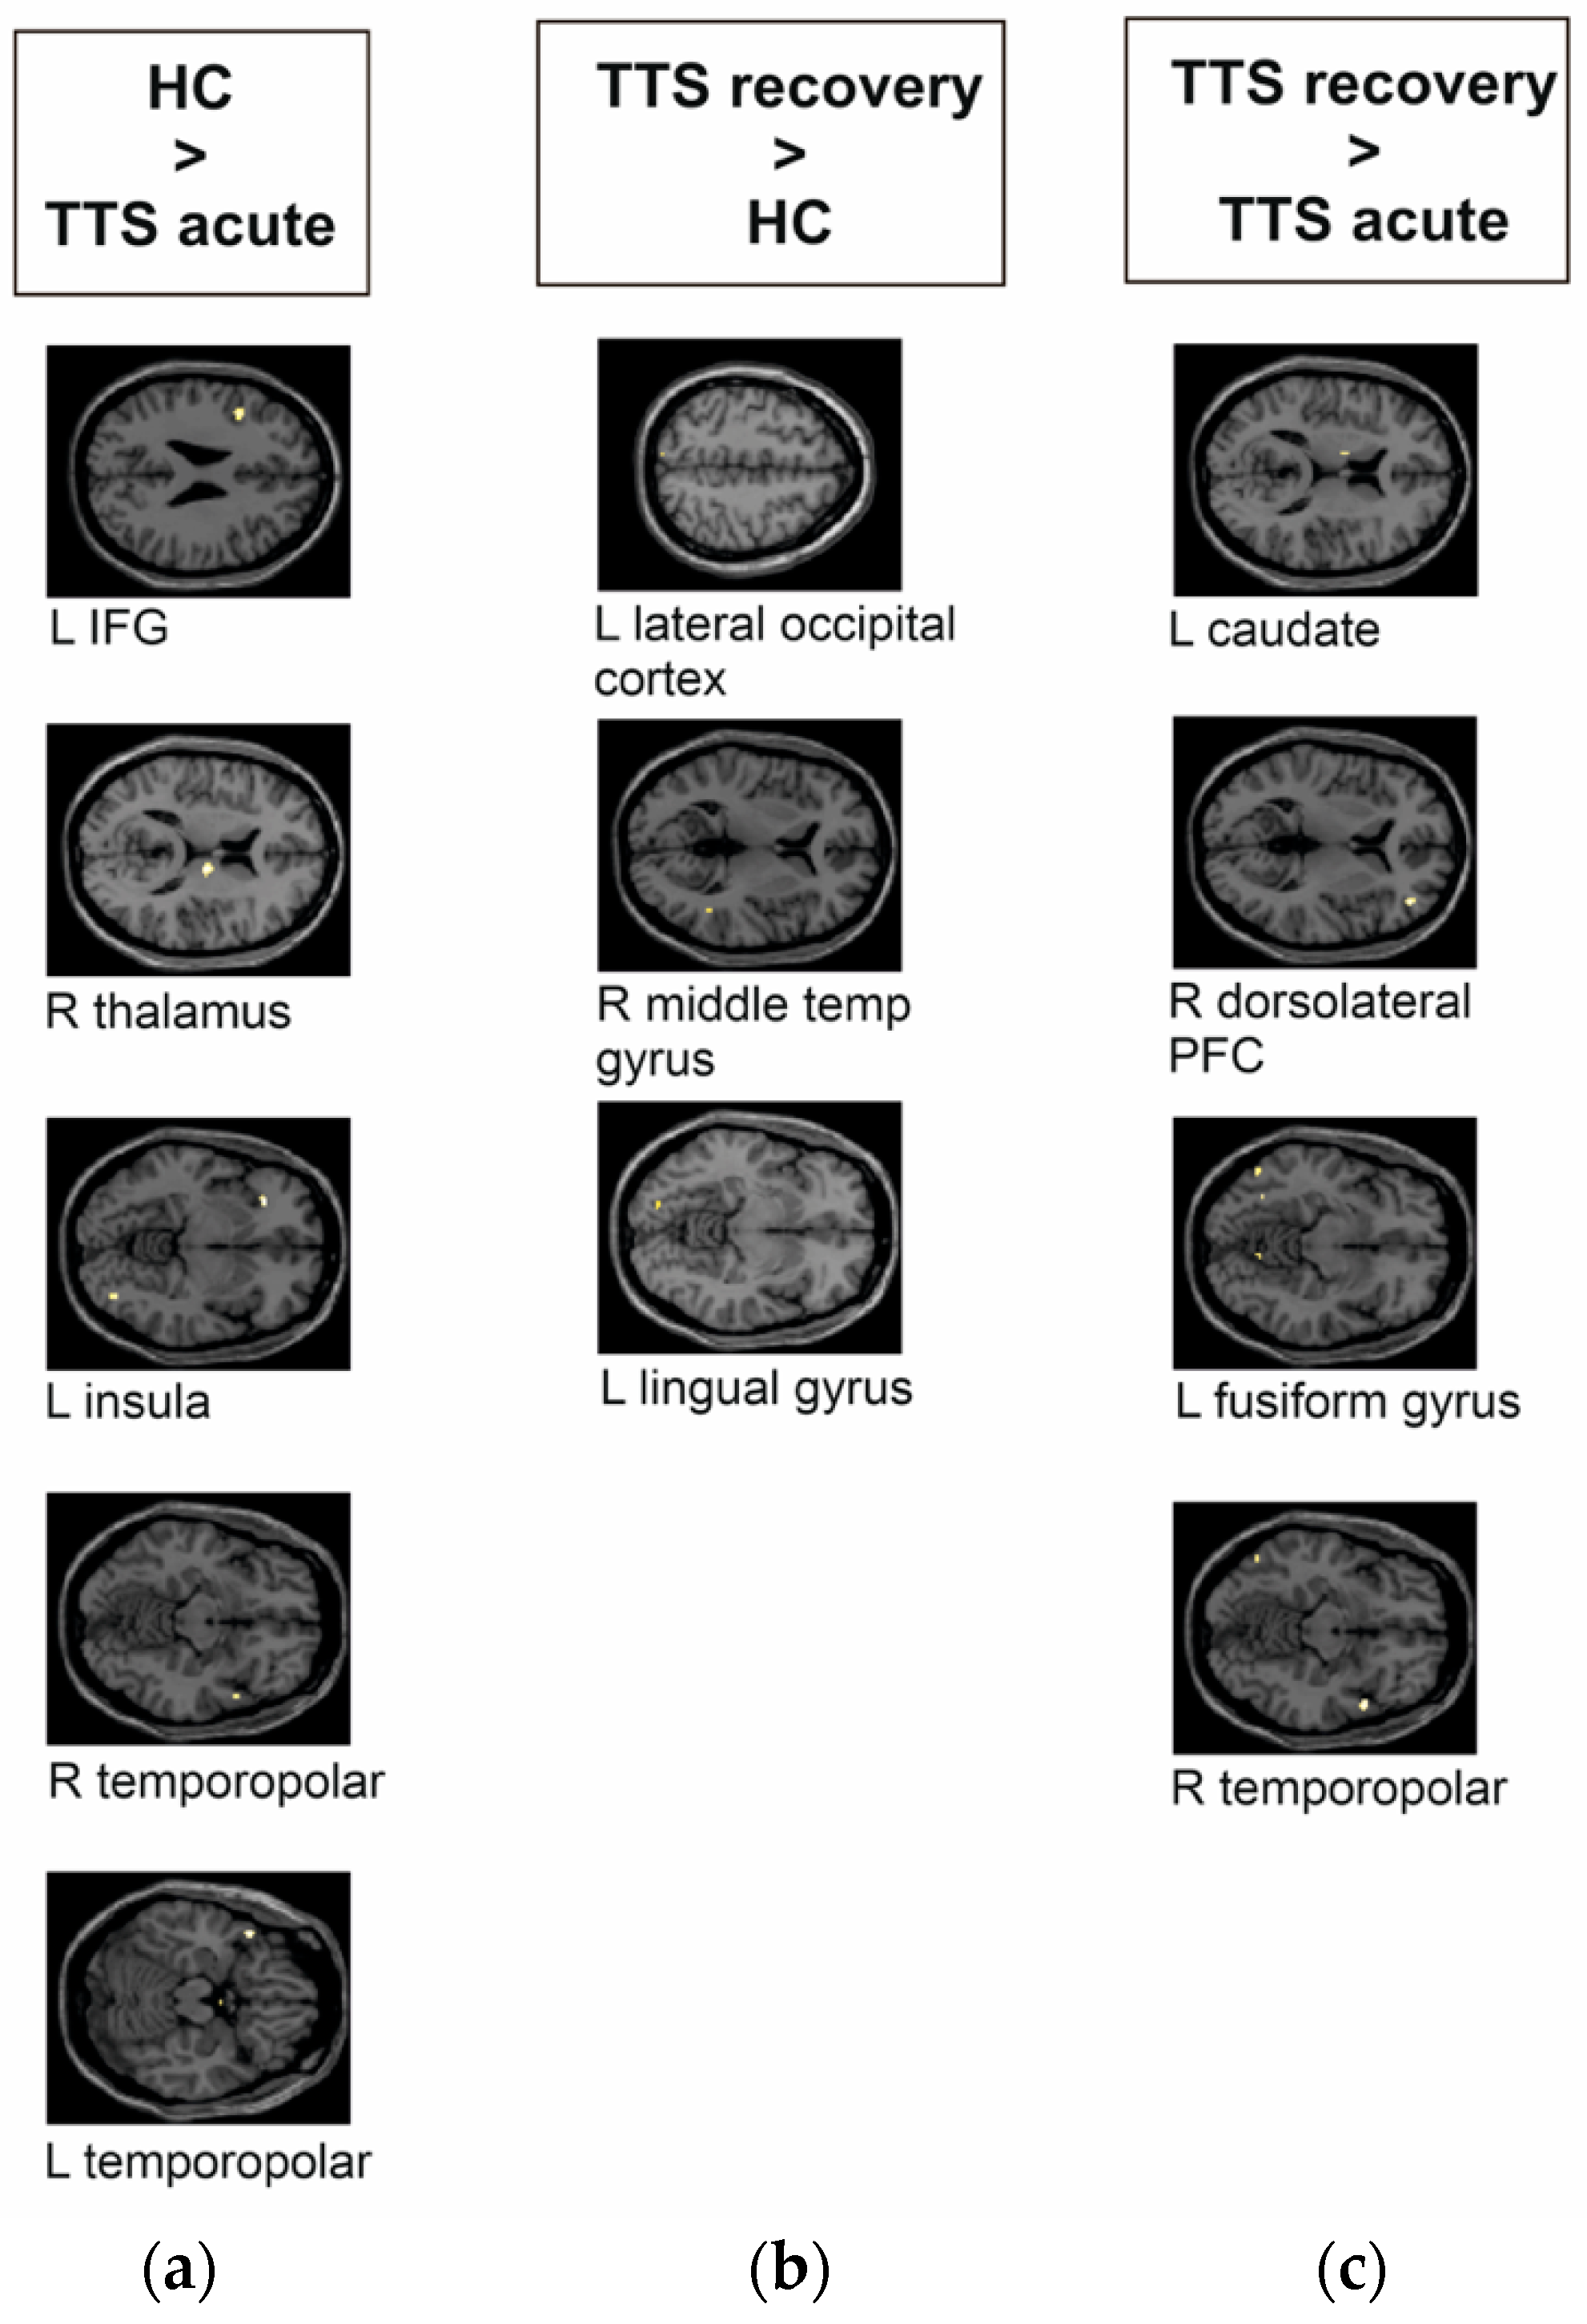

| Group Contrast | Number of Voxels | MNI Coordinate | Region | T Value | p Value |

|---|---|---|---|---|---|

| TTS acute phase < HC | 40 | −42, 12, 26 | L IFG | 3.86 | 0.000 |

| 39 | 14, −12, 14 | R thalamus | 4.21 | 0.000 | |

| 26 | −28, 28, −6 | L insula | 4.15 | 0.000 | |

| 13 | −46, 18, −18 | L temporopolar | 4.19 | 0.000 | |

| 6 | 56, 10, −12 | R temporopolar | 3.62 | 0.001 | |

| TTS recovery phase > HC | 5 | −16, −84, −8 | L lingual gyrus | 3.67 | 0.001 |

| 5 | −8, −80, 52 | L lateral occipital cortex | 3.55 | 0.001 | |

| 2 | 46, −46, 6 | R middle temporal gyrus | 3.59 | 0.001 | |

| TTS recovery phase > TTS acute phase | 25 | 42, 44, 6 | R dorsolateral PFC | 4.24 | 0.000 |

| 19 | 56, 10, −12 | R temporopolar | 4.14 | 0.000 | |

| 9 | −12, −4, 14 | L caudate | 3.65 | 0.001 | |

| 8 | −52, −66, −10 | L fusiform gyrus | 3.67 | 0.001 |